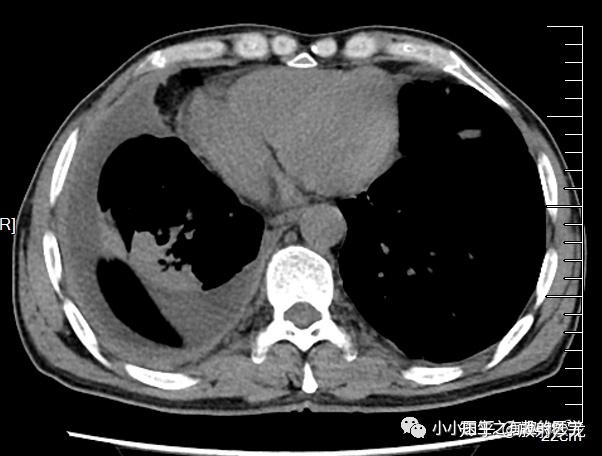

游离性胸腔积液